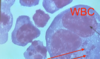

Leishmania sp.: Amastigotes

Divided & intracellular - Only in macrophages